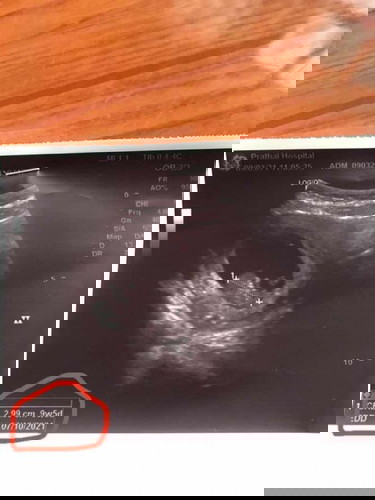

ตรงนี้คืออายุครรภ์ไหมคะ ถ้านับประจำเดือนครั้งสุดท้ายหมอบอกอายุครรภ์10สัปดาห์คะ

ใช่ค่ะ 9w5d ค่ะ